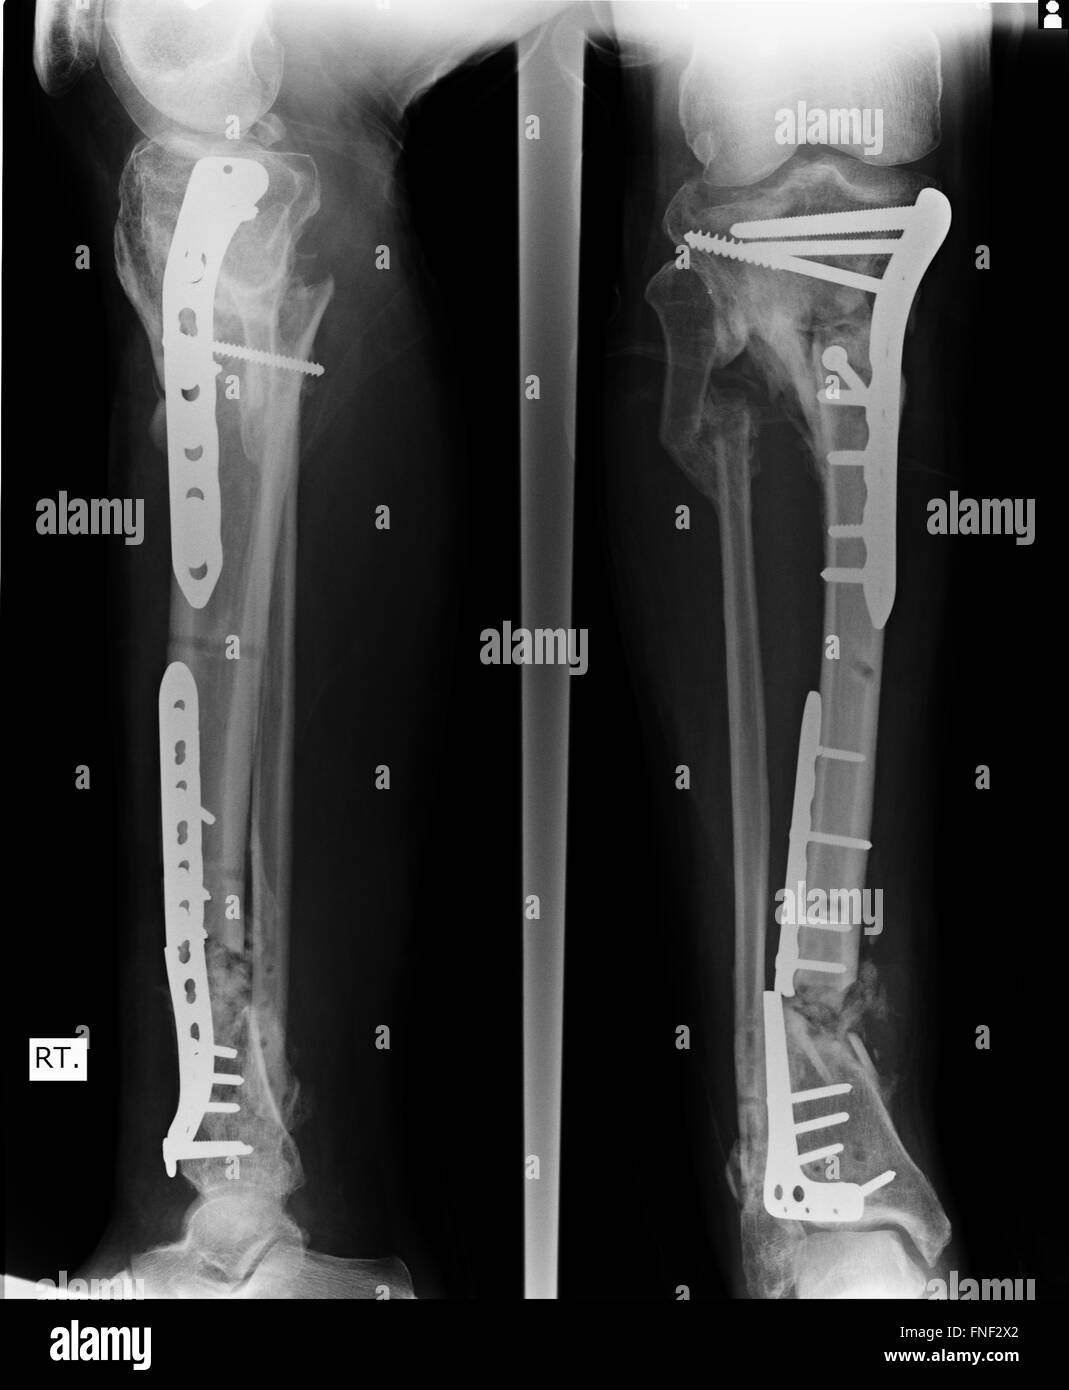

From www.alamy.com

Fracture Elbow, forearm xrays image showing plate and screw fixation Removing Plate And Screws From Elbow in order to remove the implant from the bone, there is typically a weakening of the bone. Screws removed to leave a hole in the bone, plates. metalware includes plates, screws, rods and wires. for planned partial removal of hardware such as plates, nails, screws or as a bail out. All the plate does is. This article. Removing Plate And Screws From Elbow.